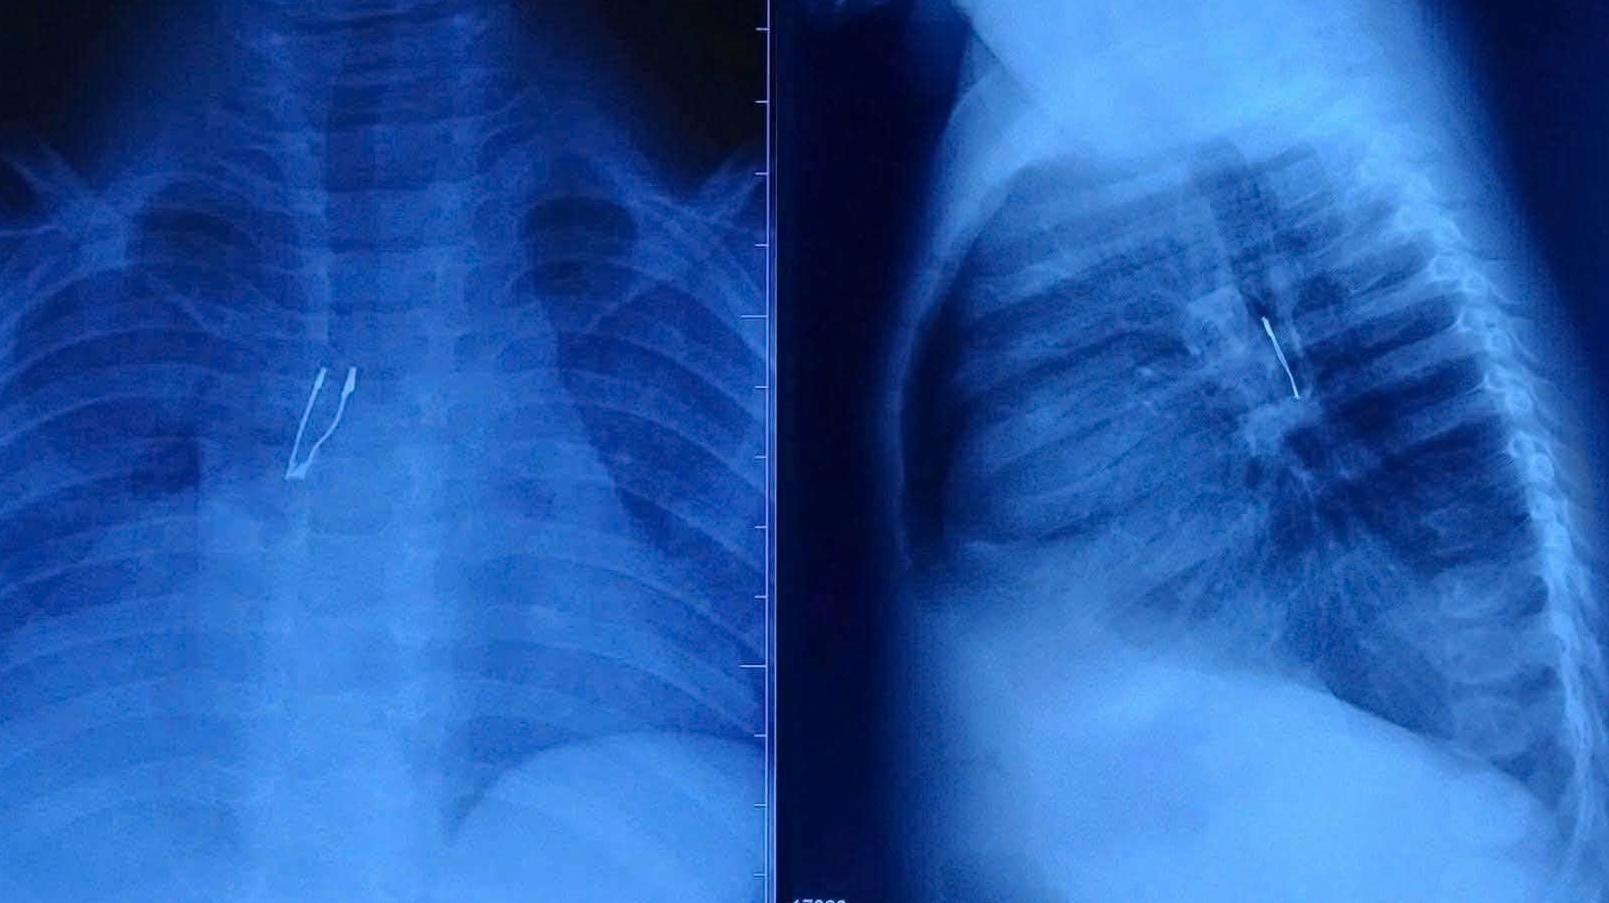

Sau 2 ngày ho nhiều, bệnh nhi 9 tháng tuổi được chẩn đoán mắc dị vật bóng đèn LED sâu trong phế quản, có dấu hiệu xẹp phổi phải chưa hoàn toàn và tràn khí trung thất.

Tại Bệnh viện Nhi đồng 1, kết quả chẩn đoán cho thấy dị vật cản quang nằm ở phế quản gốc phải, kèm dấu hiệu xẹp phổi phải chưa hoàn toàn và tràn khí trung thất – những biến chứng tiềm ẩn nguy cơ nặng. Ngay lập tức, ê-kíp Khoa Tai Mũi Họng đã hội chẩn liên chuyên khoa, phối hợp gây mê tiến hành nội soi phế quản cấp cứu.

Hình ảnh dị vật nằm sâu trong phế quản. Ảnh: BVCC.

Dị vật được xác định là một bóng đèn LED mắc kẹt sâu trong phế quản gốc phải. Quá trình gắp gặp nhiều khó khăn do cấu trúc đuôi đèn bè, sắc nhọn, dễ gây tổn thương khi kéo qua thanh quản. Với đường thở của trẻ còn rất nhỏ, bác sĩ phải xoay chỉnh dị vật từng chút một để đưa phần đầu ra trước, hạn chế tối đa nguy cơ trầy xước hoặc rách niêm mạc.